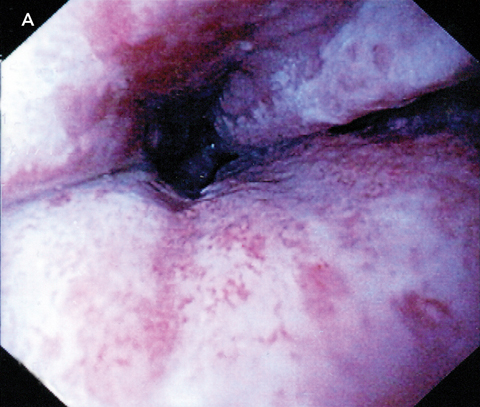

There was no other relevant medical history. The patient was a non-smoker and consumed only small amounts of alcohol. Results of a physical examination, electrocardiogram and chest x-ray were all normal. Upper gastrointestinal endoscopy revealed circumferential ulceration, with clearly visible submucosa of the distal 8 cm of the oesophagus (Box A). The stomach was normal. There was patchy erythema in the first part of the duodenum, but the second and third parts were normal. Histological examination of oesophageal biopsies demonstrated only granulation tissue. Duodenal biopsies were normal.